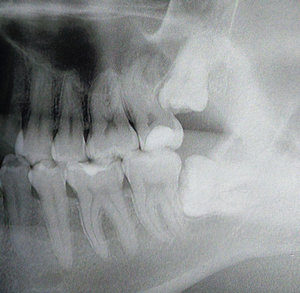

У меня растет 8-й зуб на нижней челюсти, а рядом нужно лечить 7-ку, пульпит. Сейчас наложили временную пломбу. У меня болит 7-ка и 8-ка. Болит горло, пришла опять на прием. Сказали, что 8-ку надо удалять, ей не хватает места. Хотелось бы узнать может можно 7-ку удалить, который больной зуб, у него еще и половины нет зуба, еще и не дают гарантию, что он не будет болеть после лечения. А 8-ку сказали, что в три этапа нужно удалять и операция это сложная.

Без снимка что-то сказать насчет 8-ого зуба сложно. Если доктора сказали, что ему мало места, скорее всего он уже принял какое-то положение. Например, растет в щеку или упирается в 7-й зуб. Операция удаления 8-ого зуба, действительно может быть не простой, но сложности в основном для хирурга, а не для Вас. В послеоперационный период может поболеть больше, чем после удаления любого другого зуба, но Вам назначат обезболивающие препараты.